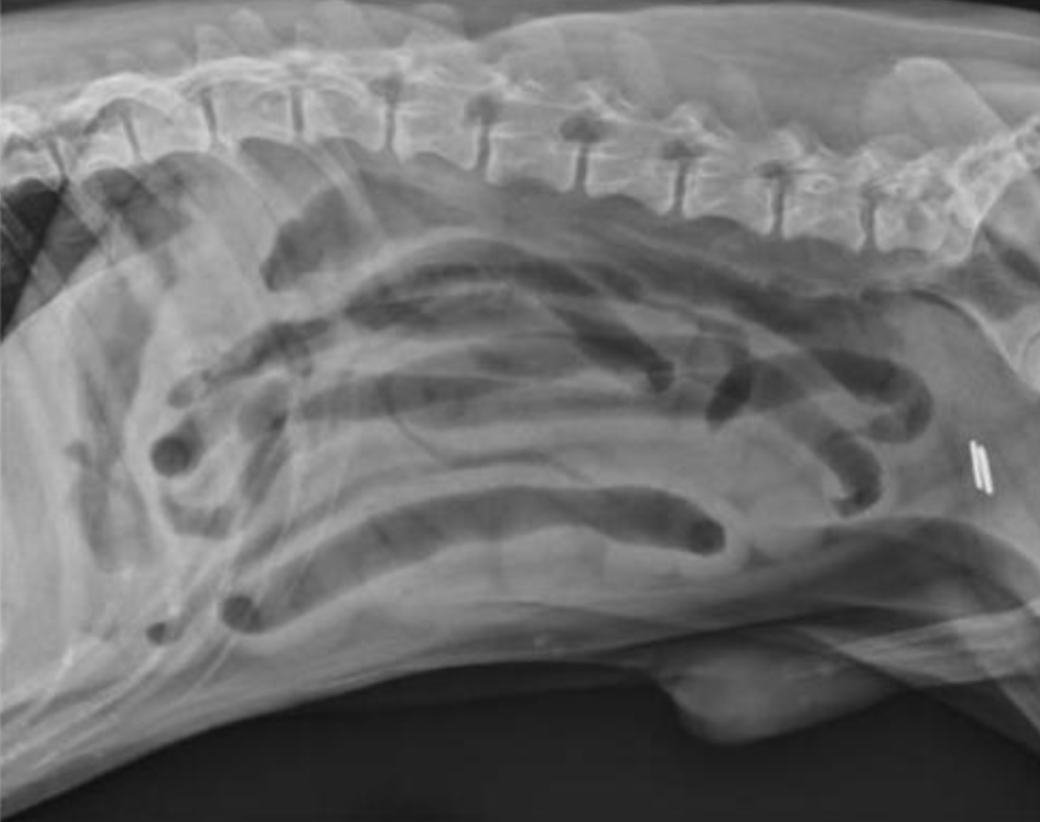

Un segment isolé d’intestin grêle sévèrement dilaté est visible chez ce chien. Son diamètre correspond à trois fois la hauteur du centre du corps vertébral de L5. Plusieurs anses d’intestin grêle sont visibles caudalement à la rate et ventralement au contenu fécal colique.Un segment de trognon d’épi de maïs, non visible radiographiquement, localisé dans le jéjunum proximal, était à l’origine de l’obstruction. d’après Thrall, Textbook of Veterinary Diagnostic Radiology, 8ᵉ édition

Ce chien présente une dilatation généralisée légère de l’intestin grêle. La majorité des segments sont remplis de gaz, avec des quantités variables de gaz intraluminal. La paroi intestinale paraît épaissie, mais cet aspect est probablement lié à un effet de silhouette entre le liquide intraluminal et la paroi, plutôt qu’à un véritable épaississement pariétal. Ce chien présentait un historique de diarrhée du grêle et du gros intestin. Les modifications radiographiques observées sont compatibles avec une entérite, mais non diagnostiques.d’après Thrall, Textbook of Veterinary Diagnostic Radiology, 8ᵉ édition